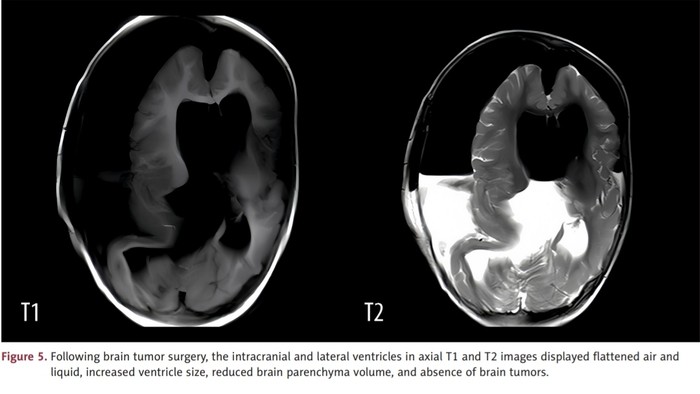

Dokter di China melaporkan kasus seorang anak perempuan berusia 1 tahun lahir dengan satu janin yang 'terperangkap' di dalam kepalanya. Ahli bedah langsung melakukan operasi karena pasien mengalami pembengkakan kepala parah, tetapi ia meninggal dua minggu kemudian karena kerusakan pada otaknya. (Foto: American Journal of Case Reports.)